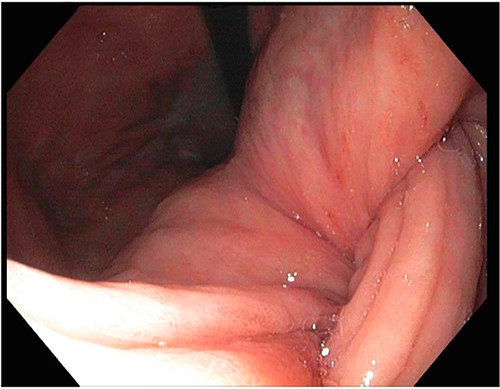

A 72-year-old patient with no past surgical history and a past medical history of developmental delay, hypertension and hyperlipidemia presented to the Emergency Department in mild distress with periumbilical abdominal pain, nausea and intractable vomiting for 1 day. The patient denied any hematemesis, bowel changes, fever, melena or hematochezia. On physical exam, the abdomen was unremarkable, and a computed tomography (CT) scan with contrast of abdomen and pelvis revealed a 5.6 × 5.3 cm heterogeneous mass arising from the body of the stomach extending into pylorus with no evidence of bowel obstruction and liver metastasis (Fig. 1). Subsequently, esophagogastroduodenoscopy (EGD) showed a large, fungating and ulcerated mass and it was reported to involve two-thirds of the luminal circumference in the gastric body (Fig. 2). Cold forceps biopsy showed gastric mucosa with hyperplastic changes, mild chronic active antral gastritis with focal intestinal metaplasia, negative for Helicobacter Pylori and dysplasia. Surgical management was discussed with the family, but they refused any surgical intervention.

CT scan image of abdomen showing heterogenous gastric mass (red arrow).